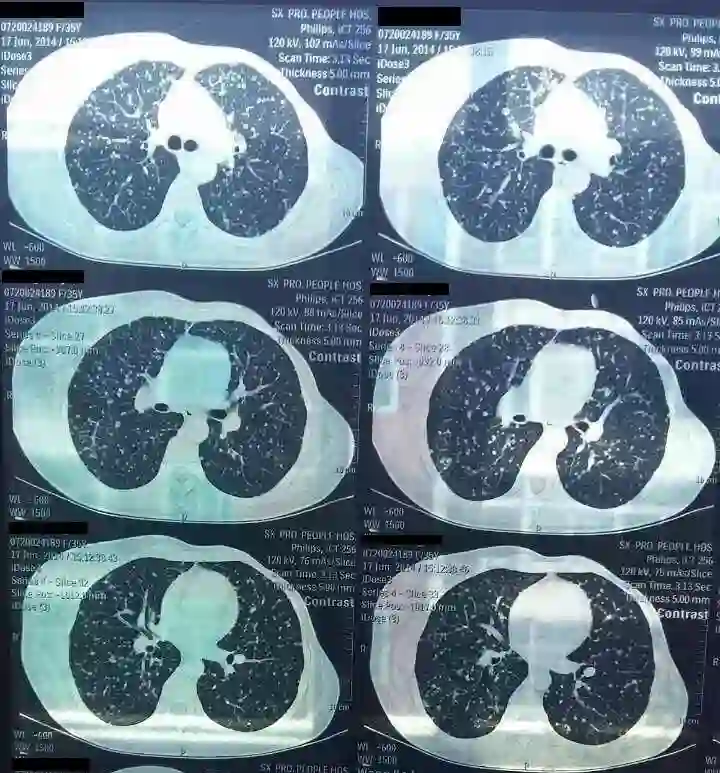

2014年6月,患者因“咳嗽进行性加重1个月”就诊,胸部CT(图1)示:左乳腺癌术后,左侧乳腺未见显示,右侧乳腺腺体内可见多发低密度影及点状高密度钙化影。双肺可见多发大小不等的结节影,结合病史考虑为转移。双侧胸廓对称,纵隔居中,内未见明显肿大淋巴结。

图1 复查胸部CT发现复发(2014年6月)